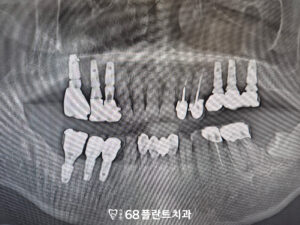

그리고 기존 임플란트의 보철을 모두 제거한 후,

전체적으로 함께 보철물을

새롭게 제작하여

임플란트와 송곳니의 조화로운 기능과

미소를 완성하였습니다.

형태와 색상을 모두 자연스럽게 맞추어,

환자분과 함께 상의 후

영구접착을 진행하였습니다.